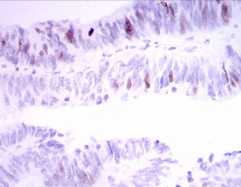

IHC    1/200 - 1/1000